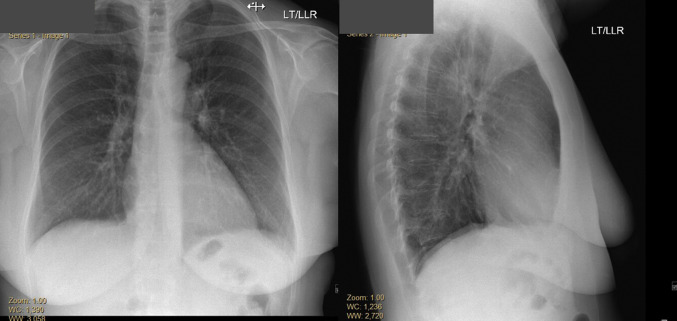

Her initial electrocardiogram demonstrated sinus tachycardia, ST-segment elevation in leads V1, V2, and aVR, and ST-segment depression in multiple other leads (Figure 1 ). Her chest X-ray showed a normal heart size; normal pulmonary vasculature; and absence of focal consolidation, pleural effusion, or pneumothorax (Figure 2 ). Laboratory testing at presentation revealed a significantly elevated high-sensitivity troponin T (hs-TnT) of 1,737 ng/L (normal 0-14 ng/L) (Table 1 ). Cardiology consultation was requested.

Figure 2.

Chest X-Ray at Presentation

Chest X-ray, anteroposterior and lateral view showing normal heart size and pulmonary vasculature. No focal consolidations, pleural effusions, or pneumothorax.